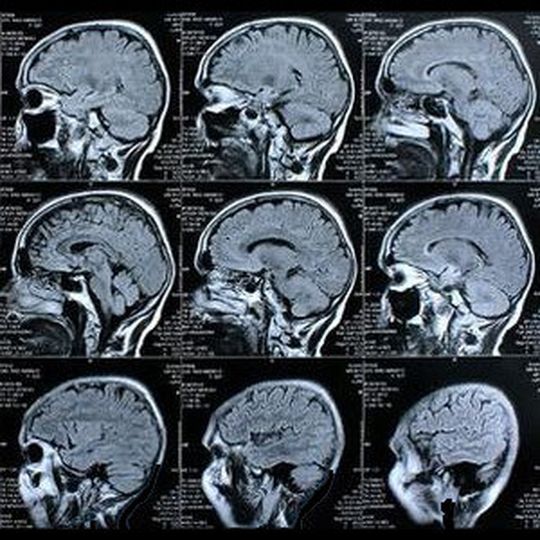

Biokompatibler Mikrochip Organischer Chip untersucht Gehirnzellenaktivität

Italienische Forscher erhoffen sich von einem neuen biokompatiblen organischen Mikrochip Fortschritte in der Hirnforschung. Der Chip soll sich wegen seiner Beschaffenheit länger im neuronalen Gewebe befinden können ohne dem Menschen zu schaden.

Das Istituto per lo Studio dei Materiali Nanostrutturati und das italienische Istituto per la Sintesi Organica e la Fotoreattività haben eine innovative Technik zur Untersuchung der Gehirnzellentätigkeit entwickelt. Mit dem "Organic Cell Simulating and Sensor Transistor" (OSCT) öffnen sich neue Wege zur Regeneration von Nervengewebe, das durch Traumata oder Parkinson geschädigt wurde. Auch hoffen die Experten auf eine Verbesserung der präventiven Diagnose von epileptischen Phänomenen.

Bei OSCT handelt es sich um einen biokompatiblen organischen Mikrochip, der elektrische Impulse erzeugen und aufzeichnen kann. "Ein besonderer Vorteil besteht darin, dass er auch längere Zeit mit neuronalem Gewebe in Kontakt sein kann, ohne eine nachteilige oder gar schädigende Wirkung auszuüben", erklärt Projektleiter Michele Muccini gegenüber pressetext.

Gleichzeitig ermöglich das Hightech-Bauteil ein besseres Verständnis der Funktionsweise von Nervenzellen und eine im Vergleich zu den herkömmlichen Verfahren effizientere Beeinflussung ihrer Tätigkeiten. "Schließlich liefert die Methode auch die Möglichkeit, andere Neuronenarten zu analysieren und damit signifikante Fortschritte in der Hirnforschung zu erzielen", so der italienische Wissenschaftler.